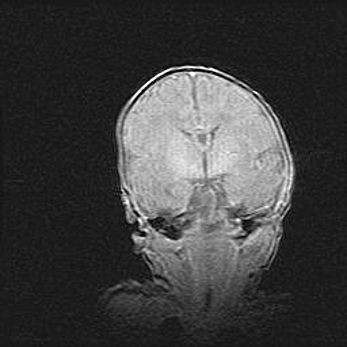

Открытая гидроцефалия.

Возраст: 6 месяцев 15 дней

Вес: 6200 г

Пол: женский

Окружность головы: 41 см

Срок гестации: 38 недель

Гидроцефалия головного мозга у новорожденных – это скопление избыточного количества цереброспинальной жидкости в головном мозге. Ее избыточное скопление в мозге приводит к патологическому расширению желудочков мозга (четырех полостей, расположенных в глубине белого вещества мозга, заполненных цереброспинальной жидкостью и связанных узкими проходами).

Открытый тип гидроцефалии (сообщающаяся) наблюдается тогда, когда нарушен механизм всасывания ликвора в системный кровоток. При этом типе причиной заболевания чаще всего является перенесенные ранее инфекции (например: менингит),  либо же наличие крови в субарахноидальном пространстве.